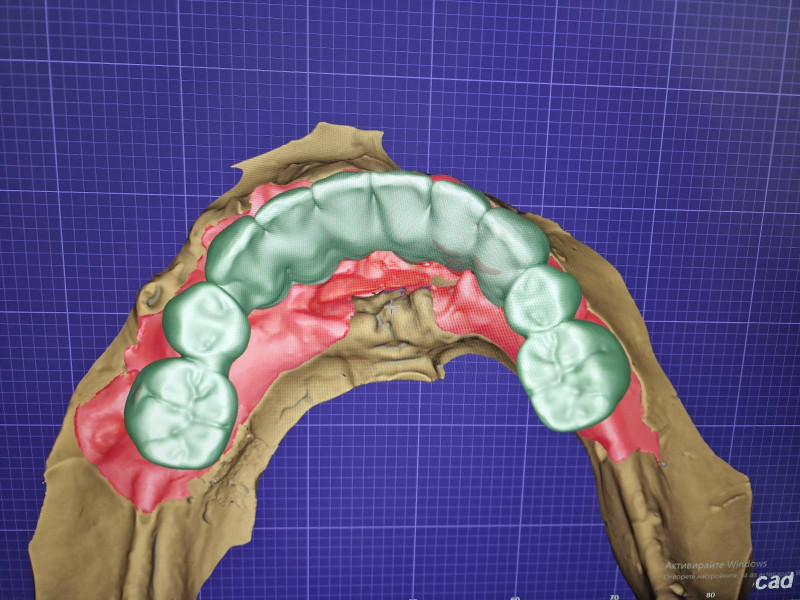

Компютърен моделаж на бъдещия мост – поглед отгоре